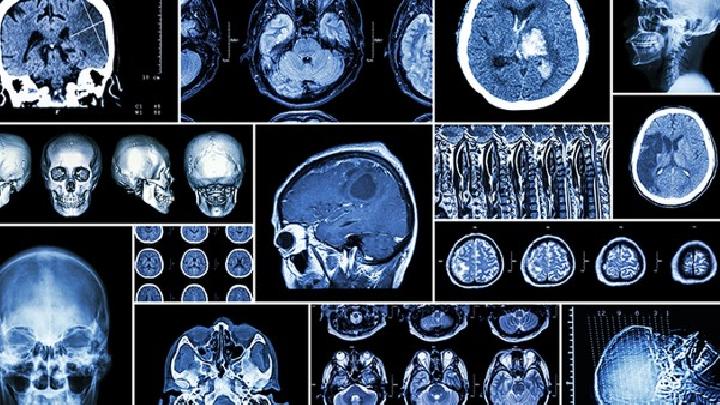

脑萎缩

以上是容易引起轻度脑萎缩的人。如果你是这些群体中的轻度脑萎缩患者,你应该提高警惕,提前做好脑萎缩的预防工作。由于脑萎缩发病缓慢,不易被发现,建议易发人群定期到医院进行脑部检查早期发现和积极适当控制病情对其治疗具有重要意义。